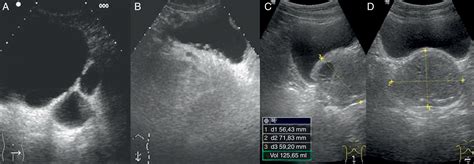

Vejiga ecografia posicion refers to the ultrasound examination of the bladder in different positions. This diagnostic tool uses high-frequency sound waves to create images of the bladder, helping healthcare providers assess its size, shape, and any abnormalities. The procedure is non-invasive and provides valuable information about the bladder's health and function.

• Ultrasound Probe: A handheld device called a transducer will be moved over the abdomen to capture images of the bladder.

• Image Capture: The technician will capture images and videos of the bladder, which will be reviewed by a radiologist.

After the vejiga ecografia posicion, the images are analyzed by a radiologist who looks for various indicators:

• Bladder Wall Thickness: Thickening of the bladder wall can indicate inflammation or other issues.

• Bladder Volume: The volume of urine in the bladder can help assess bladder function.

• Presence of Abnormalities: The presence of stones, tumors, or other abnormalities will be noted.

• Residual Urine: The amount of urine left in the bladder after voiding can indicate bladder outlet obstruction.